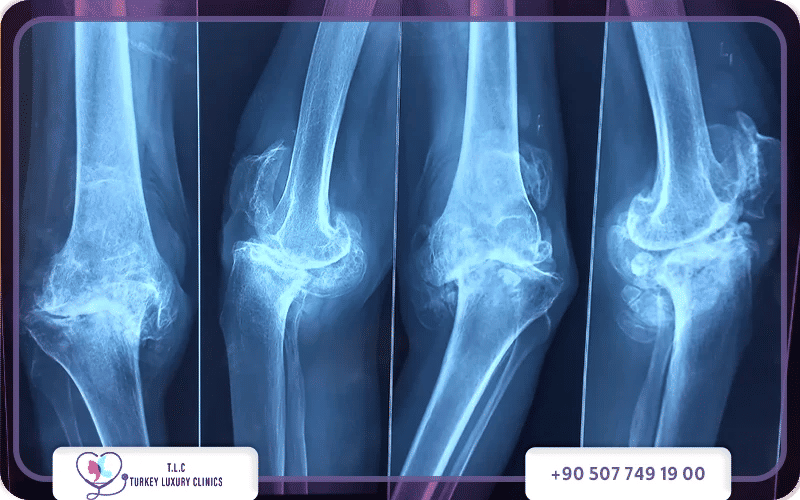

يظهر شكل خشونة الركبة بالصور بوضوح عبر تآكل الغضاريف التي تحمي نهايات العظام، و تضيق المساحة المفصلية وظهور نتوءات عظمية مؤلمة، حيث تبدأ بتآكل بسيط غير مرئي، وتتطور لتصل إلى احتكاك العظام المباشر وتشوه المفصل وتورمه بشدة.

يظهر شكل خشونة الركبة بالصور على هيئة ضيق المسافة بين عظام المفصل، وتكون نتوءات عظمية، وتقوس في الساقين في الحالات المتقدمة. تبدو الركبة المصابة بتورم، واحمرار، وأحياناً اعوجاج ظاهر عند المشي.

يبدو شكل خشونة الركبة بالصور على هيئة تضيق في المسافة بين عظام مفصل الركبة نتيجة تآكل الغضروف الذي يغطي أطراف العظام، يعمل هذا الغضروف كوسادة مرنة تمتص الصدمات وتمنع احتكاك العظام ببعضها، ومع تآكله التدريجي تبدأ التغيرات بالظهور جلياً في صور الأشعة.

توضح صور الأشعة السينية شكل خشونة الركبة بالصور بشكل دقيق، حيث يمكن ملاحظة تضيق المسافة المفصلية بين عظم الفخذ وعظم الساق، كما قد تظهر زوائد أو نتوءات عظمية حول حواف مفصل الركبة، وتساعد هذه العلامات الأطباء على تقييم شدة الخشونة وتشخيص الحالة.

يختلف شكل خشونة الركبة بالصور باختلاف درجة المرض؛ في المراحل المبكرة يظهر تضيق بسيط في المسافة بين العظام دون تغيرات كبيرة في المفصل، أما في المراحل المتوسطة فتبدأ الزوائد العظمية بالظهور مع تآكل أكبر في الغضروف.

في المراحل المتقدمة وخاصة في الدرجة الرابعة، يصبح شكل خشونة الركبة بالصور أكثر وضوحاً حيث تختفي المسافة المفصلية تقريباً، ويؤدي ذلك إلى احتكاك مباشر بين العظام فيما يعرف بمرحلة "العظم على العظم"، وتترافق هذه المرحلة مع ألم شديد وصعوبة في الحركة.

درجة الخشونة | شكل الركبة في الأشعة السينية (X-ray) | مظهر الركبة الخارجي |

الدرجة الأولى | نتوءات عظمية صغيرة جداً ومسافة طبيعية. | طبيعي تماماً ولا يوجد تورم. |

الدرجة الثانية | نتوءات واضحة مع بداية ضيق بسيط في المسافة. | تورم بسيط عابر بعد الجهد. |

الدرجة الثالثة | ضيق واضح في المسافة وتآكل ملموس للغضاريف. | تورم واضح وتغير طفيف في الشكل. |

الدرجة الرابعة | اختفاء المسافة تماماً (احتكاك عظم على عظم). | تشوه مرئي (تقوس) وتضخم كبير. |

تقسم درجات خشونة الركبة إلى 4 درجات أساسية، ويمكن التمييز بينها تبعاً لنتائج الصور بالأشعة السينية، وصور الرنين المغناطيسي، بالإضافة إلى الأعراض السريرية المرافقة لكل حالةٍ منها.

شكل خشونة الركبة من الدرجة الرابعة بالأشعة

يختفي الغضروف المفصلي تماماً، وتحتك العظام ببعضها مباشرةً. تظهر المسافة المفصلية ضيقة جداً أو تكاد تختفي تماماً، مع ملاحظة نتوءات عظمية كبيرة وتصلب في العظم أسفل الغضروف وتغير واضح في شكل سطح العظام.